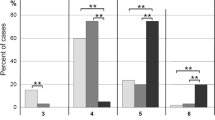

Survey of the literature using PubMed revealed a number of cases with co-occurring Lewy body pathology and gliomas, including 2 anaplastic astrocytomas, 1 glioblastoma, and 1 gliomatosis cerebri (Table 1). First, these patients are older with a median age of 72 (range 61–77). Negative immunohistochemical staining for IDH-1 mutation was reported in 2, consistent with the typical profile in this older population [19]. Second, most of the cases were found to have Lewy body pathology at the brainstem, inferior frontal lobes and temporal lobes similar to our patient. Lastly, two had external beam radiation therapy, one received 4,000 cGy ionizing radiation to the right temporal lobe after biopsy [20]) and the other had the equivalent of 5,300 cGy from boron-neutron capture heavy particle therapy to the right parietal brain [21]. Only the latter was Lewy body pathology identified in the brainstem post-mortem, and the authors concluded that boron-neutron therapy was safe because this region only received an equivalent of 1,700 cGy of radiation [21]. In contrast, our patient received a much higher dose or 3,000 cGy to the brainstem, and therefore his neurologic vulnerability from Lewy bodies and the higher radiation dose could contribute in a synergistic fashion to his rapid deterioration after treatment.